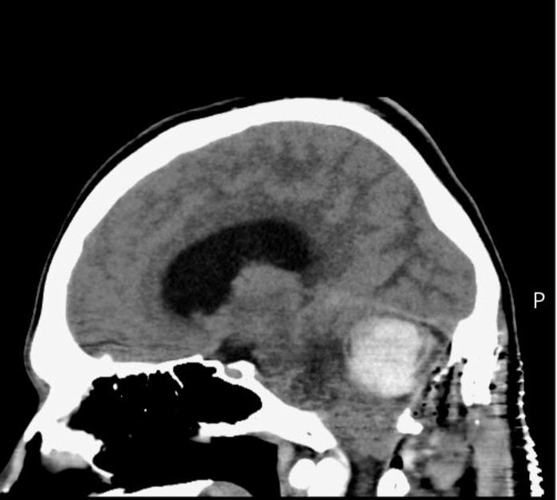

Luke Taylor's brain scan. (Nia Jones via SWNS)

In July 2025, Luke was diagnosed with a haemangioblastoma - a very rare brain tumour.

By the time of diagnosis, the tumour had grown so large - bigger than a golf ball - that Luke was told he only had days to live without emergency surgery.

He demanded an MRI scan and the results came back showing that Luke had a haemangioblastoma  - a very rare brain tumor that can grow throughout the brain and spinal cord.